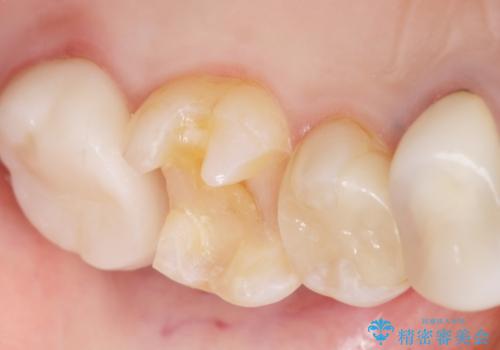

銀歯の下が虫歯になっている セラミックインレー 30代女性

- 奥歯がたまにしみることを主訴に来院された患者様です。

精査したところ、奥歯のメタルインレー(銀の詰め物)の下でう蝕が広がっていました。

う蝕を丁寧に除去したのち、セラミックインレーによる補綴治療を行いました。